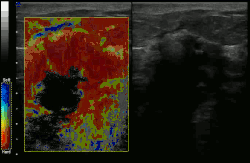

Scale is in kPa of Young's modulus

Conventional ultrasonography (lower image) and elastography (supersonic shear imaging; upper image) of papillary thyroid carcinoma, a malignant cancer. The cancer (red) is much stiffer than the healthy tissue.